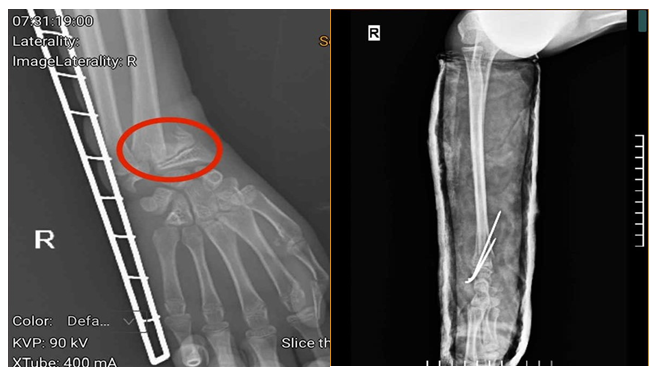

Hình ảnh phim chụp của người bệnh trước và sau khi phẫu thuật (vùng tổn thương trước phẫu thuật được khoanh đỏ) - Ảnh BVCC

Người bệnh vào viện trong tình trạng tay phải được cố định bằng nẹp, cẳng tay, cổ tay phải đau nhiều, sưng nề…

Tại Khoa Ngoại Chấn thương và Y học Thể thao, Trung tâm Chấn thương chỉnh hình, Bệnh viện Đa khoa tỉnh Phú Thọ, người bệnh được bác sĩ khám, chỉ định thực hiện các cận lâm sàng và được chẩn đoán gãy xương cẳng tay phải.

Tuy nhiên, do thời gian tổn thương kéo dài, người bệnh bị chấn thương trước khi vào viện 3 ngày, kèm theo việc gia đình cho người bệnh bó thuốc nam nên vùng xương và cơ bị tổn thương, có hiện tượng co cứng, đặc biệt, vùng xương gãy gần với sụn, nếu không can thiệp kịp thời sẽ ảnh hưởng đến khả năng vận động sau này.

Người bệnh được chỉ định phẫu thuật kết hợp xương bằng kỹ thuật C-arm với đội ngũ bác sĩ tay nghề cao, giúp nâng cao khả năng phục hồi tối đa.